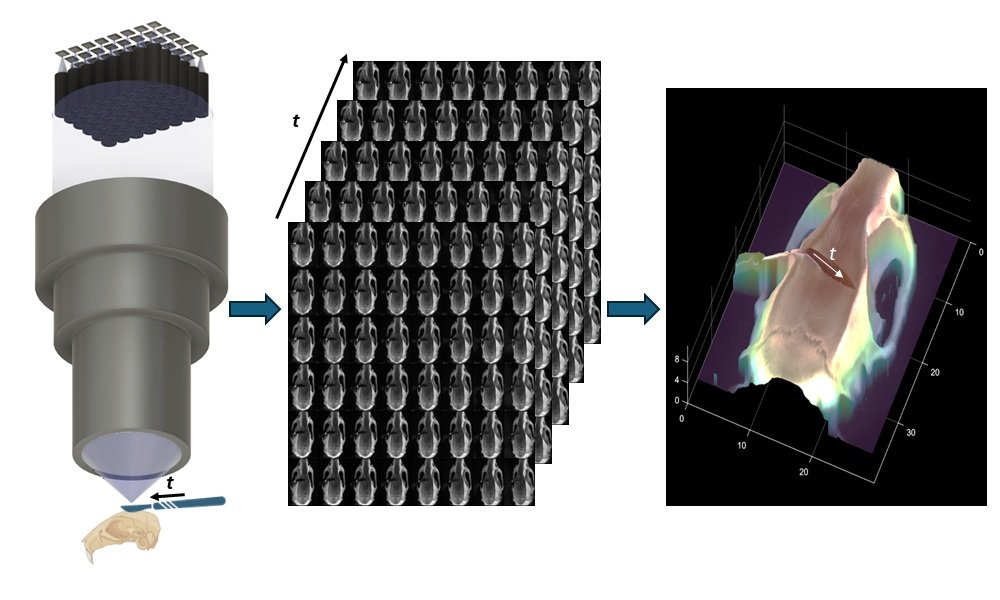

Delivering drugs to the brain has always been a high-stakes challenge. The blood-brain barrier (BBB)—a tightly regulated shield of cells—blocks over 98% of small molecule drugs, making treatment of neurodegenerative diseases like Alzheimer’s and Parkinson’s notoriously difficult. Now, researchers at […]